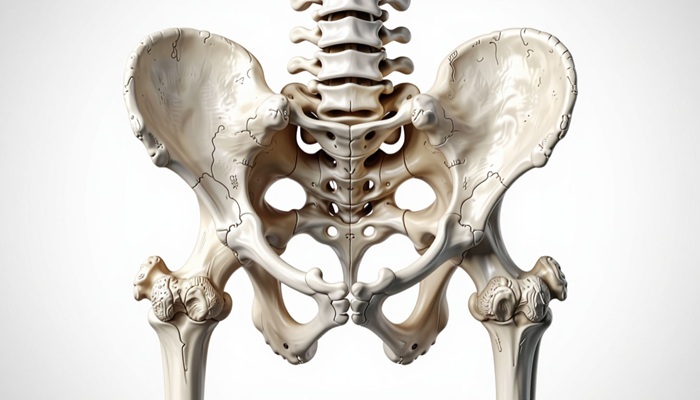

Рентген таза показывает детализировано состояние всех костей таза, строение тазобедренного сустава, основание позвоночника, а также крестцовое сочленение. На снимке достаточно отчетливо видны малый таз, сухожилия, связки.